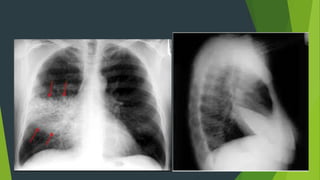

Tác dụng của phim X quang phổi nghiêng?

 Xác định vị trí của tổn thương theo thùy và phân thùy

 Chẩn đoán định hướng các khối u trung thất

 Khảo sát các vùng sau tim trái, sau vòm hoành hoặc trước rốn

phổi

 Chẩn đoán TDMP ít mà dịch khu trú ở góc sườn hoành sau không

nhìn rõ trên phim chụp thẳng